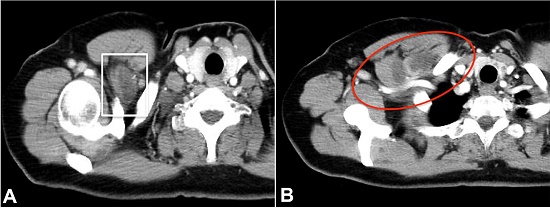

A 52-year-old woman sought the medical facility complaining of a painful tumor in the right pectoral region over the last 8 months. The patient lived in the rural area but had no contact with livestock or domestic animals. During the last 5 months, she reported two episodes of bulging mass over the right frontal chest region accompanied by inflammatory signs that subsided within 1-2 weeks. Her past medical history was unremarkable. Her blood tests were normal. However, the thoracic computed tomography (CT) depicted a 60 mm bilobed and cystic lesion in the right pectoralis minor muscle, which compressed the right subclavian vein at the exit of the costoclavicular space. These findings were consistent with cystic lymphangioma or intramuscular myxoma ( Figure 1).